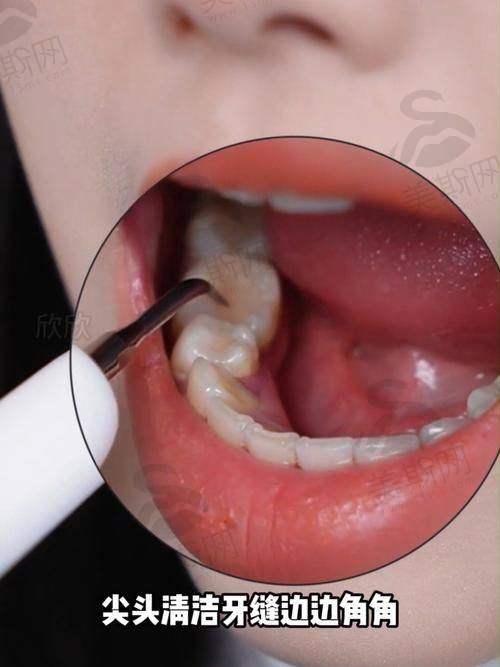

6. 牙周病系统治疗:引进瑞士EMS牙周治疗仪,实施龈下刮治+激光辅助治疗,重度牙周炎治疗有效率达89%。

8. 牙齿美白中 心:提供冷光美白、超声波洁牙等服务,采用美国Beyond美白剂,单次治疗可提升6 - 8个色阶。